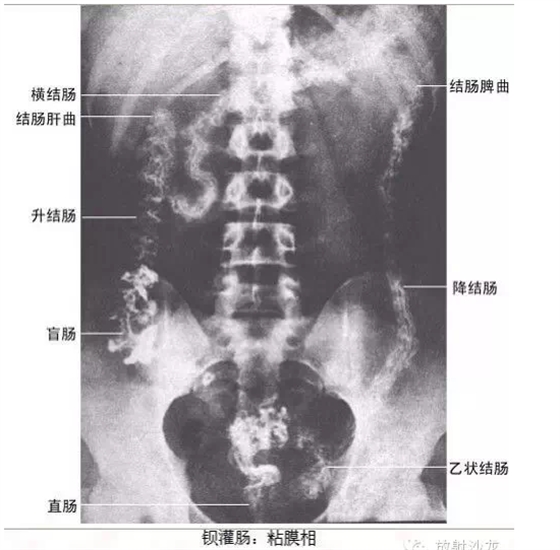

干貨!超級全的X線解剖圖